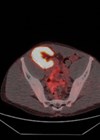

Guy’s transplant department perform a lot of operations and it is by far and away the busiest unit I have ever worked in. They perform paediatric and adult kidney transplants (more than any other unit in the UK), simultaneous pancreas kidney (SPK) transplants, living donor nephrectomies along with numerous dialysis access, urological and general surgical procedures. The department operates across multiple sites for 24 hours seven days a week. Compared to urology, the on-calls are intense, with complicated operations happening at all times through the night and weekend. This is great as the registrars are always busy in theatre and assistance is appreciated so the skills of the juniors are developed.

SPK transplant is a truly unique experience in surgery, lasting for as long as 10 hours and starting at any time. Numerous vascular, bowel and urological anastomoses are coordinated between four surgeons on one case after maximum exposure of the great vessels in the abdomen is obtained. Occasionally the entire surgical team rotates during the procedure which is not something I’d ever seen before. It was a privilege to assist on almost 10 SPK transplants in one year and you would be hard pressed to find an operation which provides better training experience for a junior surgeon.